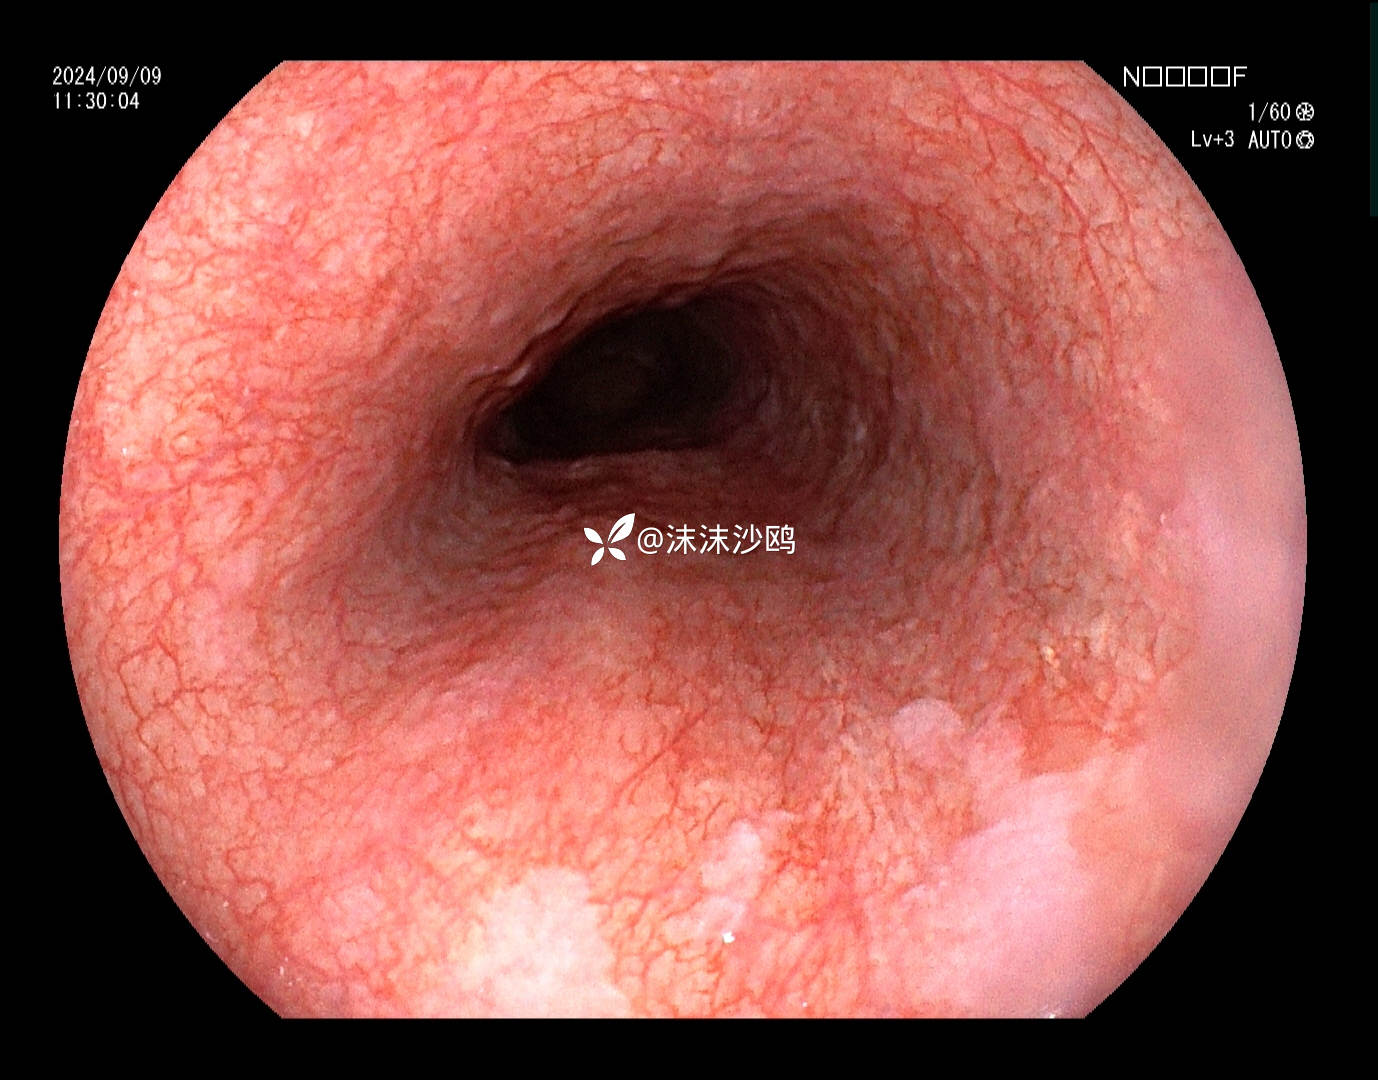

老年男性,腹胀不适门诊行普通胃镜检查。距门齿30cm见片状粘膜粗糙发红,呈0-II b型病灶。

距门齿30cm见片状粘膜粗糙发红,大小约2cm,形态0-II b型

该患者平素无明显症状,吸气注气观察病灶延展性,柔软度可,白光观察粘膜呈现发红粗糙,BLI放大观察呈现明显茶褐色,可见B1型血管,局灶可见紊乱生长的B2型血管,并见AVA区域,感觉小于0.5mm。镜下考虑浸润深度,不超过SM1,应该有内镜下D的可能性。等病理结果,希望符合内镜诊断。